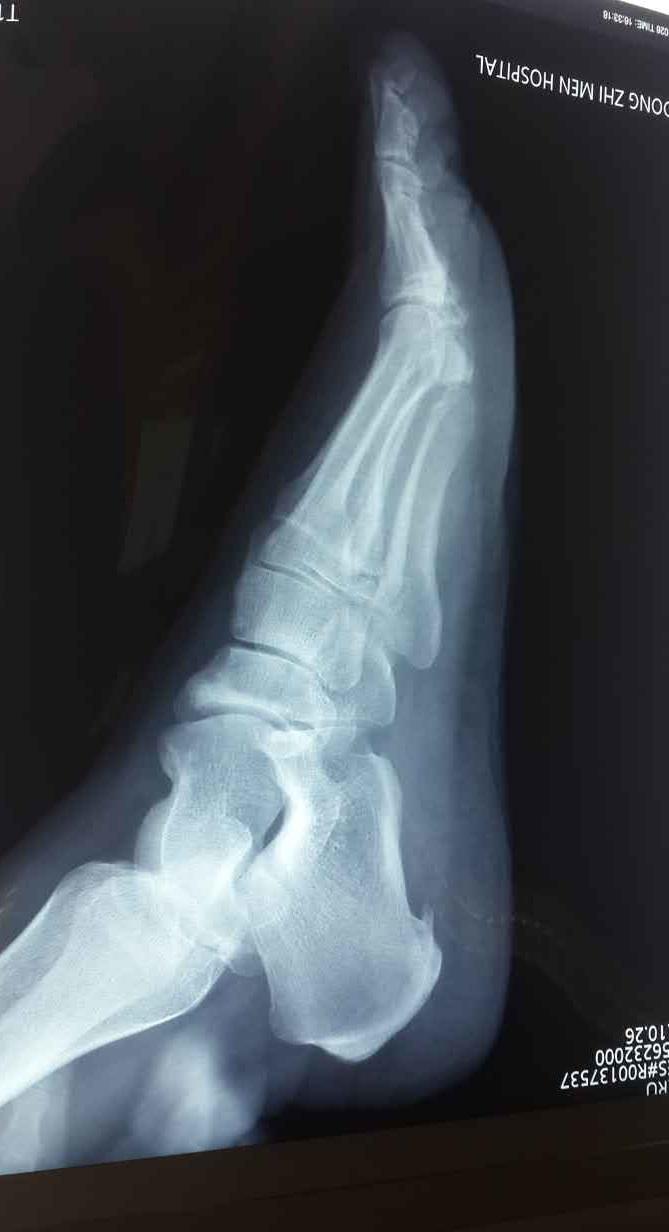

检查:左足跟部侧位X光片

诊断:左脚跟骨骨刺